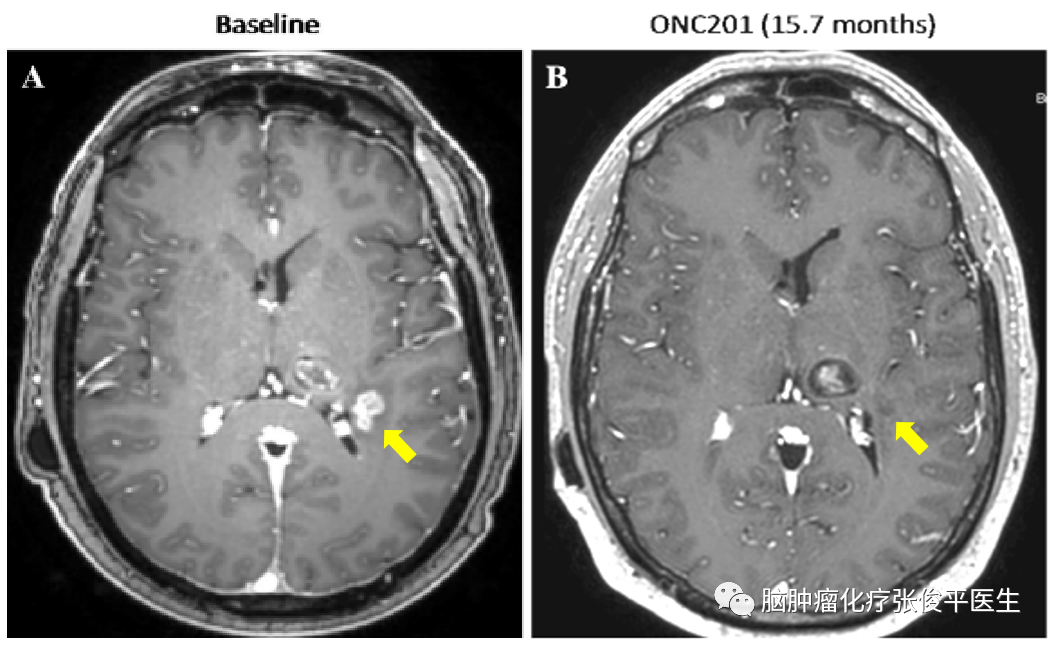

在洛莫司汀化疗结束后1个月患者开始接受ONC201治疗。第6周时复查MRI时左顶叶肿瘤增强灶减小34%,脑水肿有所改善。治疗10个月之后肿瘤消失,疗效达到CR,且头痛、恶心、右侧肢体麻木等临床症状均有所改善。